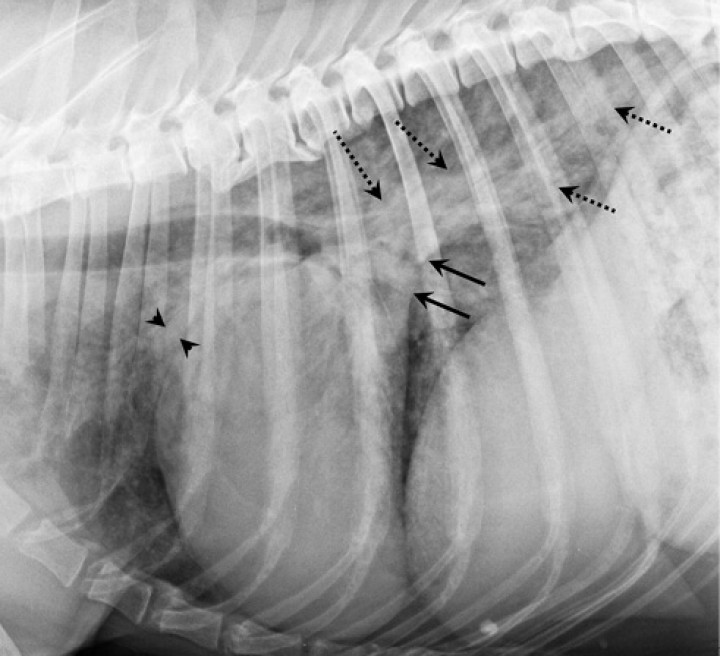

West Highland White Terrier macho castrado de 14 años presentado por tos crónica. En la proyección lateral derecha (Fig. 3A), la silueta cardíaca está aumentada de tamaño, ocupando 4 espacios intercostales (ref<2,5-3), produciendo un desplazamiento dorsal de la tráquea, adquiriendo una posición paralela respecto a la columna vertebral (flechas negras punteadas). El aumento del apoyo esternal en la vista lateral y apariencia de D invertida en la proyección DV de la Fig. 3B (mayor engrosamiento con una forma más redondeada, flechas blancas) son consistentes con cardiomegalia derecha. El cuadrante craneodorsal amplio está causado por dilatación del atrio derecho. Considerando la raza y los cambios en el parénquima pulmonar asociados, con un aumento de la opacidad pulmonar con áreas de patrón alveolointersticial, más marcado en lóbulos caudodorsales (cabezas de flecha) compatibles con posible fibrosis pulmonar, los cambios cardíacos son compatibles con un cor pulmonale por hipertensión pulmonar secundaria a la enfermedad respiratoria, afectando predominantemente al corazón derecho. También se detecta redundancia de la membrana dorsal de la tráquea (flechas negras), sugestivo pero no diagnóstico de colapso de tráquea.

<p>Perro mestizo macho castrado de 12 años presentado para la investigación de soplo cardíaco debido a enfermedad degenerativa de la válvula mitral. La radiografía de la Fig. 4A (proyección lateral derecha) muestra cardiomegalia evidente, con un aumento severo del cuadrante caudodorsal, correspondiente con la dilatación marcada del atrio izquierdo (flechas negras). Esta causa elevación de la tráquea (paralela a la columna vertebral, cabezas de flecha negra) con compresión bronquial (puntos negros) debido al aumento de tamaño del atrio izquierdo. Ambos ventrículos están incrementados de tamaño, resultando en una silueta cardíaca que ocupa aproximadamente 3,5 espacios intercostales (ref<2,5-3). La presencia de leve patrón intersticial dorsocaudal hace sospechar de fases iniciales de insuficiencia cardíaca congestiva izquierda. La radiografía de la Fig. 4B (proyección lateral derecha) corresponde al mismo paciente, mostrando progresión severa de la enfermedad, ahora en fase terminal. Muestra marcada cardiomegalia generalizada, con la silueta cardíaca ocupando unos 4 EIC, con marcado desplazamiento dorsal de la tráquea y con compresión de los bronquios. También se detecta un patrón pulmonar intersticial generalizado con áreas de marcado aumento de la opacidad pulmonar (patrón alveolar), correspondiente a edema pulmonar cardiogénico marcado, signo de insuficiencia cardíaca izquierda.</p>

Figura 4

Perro mestizo macho castrado de 12 años presentado para la investigación de soplo cardíaco debido a enfermedad degenerativa de la válvula mitral. La radiografía de la Fig. 4A (proyección lateral derecha) muestra cardiomegalia evidente, con un aumento severo del cuadrante caudodorsal, correspondiente con la dilatación marcada del atrio izquierdo (flechas negras). Esta causa elevación de la tráquea (paralela a la columna vertebral, cabezas de flecha negra) con compresión bronquial (puntos negros) debido al aumento de tamaño del atrio izquierdo. Ambos ventrículos están incrementados de tamaño, resultando en una silueta cardíaca que ocupa aproximadamente 3,5 espacios intercostales (ref<2,5-3). La presencia de leve patrón intersticial dorsocaudal hace sospechar de fases iniciales de insuficiencia cardíaca congestiva izquierda. La radiografía de la Fig. 4B (proyección lateral derecha) corresponde al mismo paciente, mostrando progresión severa de la enfermedad, ahora en fase terminal. Muestra marcada cardiomegalia generalizada, con la silueta cardíaca ocupando unos 4 EIC, con marcado desplazamiento dorsal de la tráquea y con compresión de los bronquios. También se detecta un patrón pulmonar intersticial generalizado con áreas de marcado aumento de la opacidad pulmonar (patrón alveolar), correspondiente a edema pulmonar cardiogénico marcado, signo de insuficiencia cardíaca izquierda.